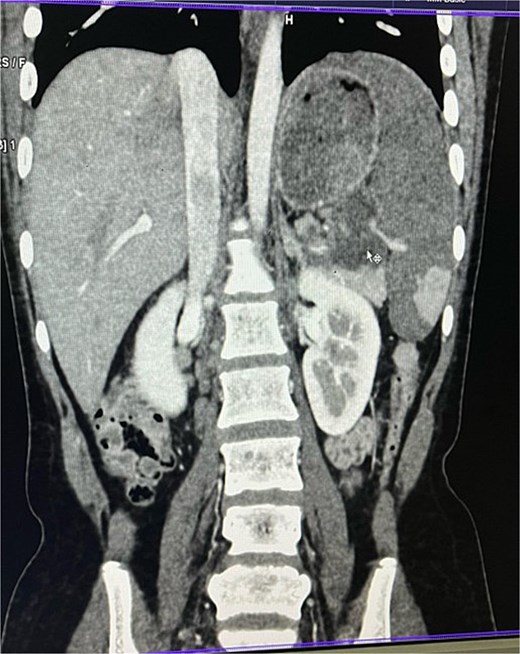

On imaging, ultrasonography showed a lobulated hypoechoic lesion in the region of the pancreatic tail and splenic hilum. This was very not conclusive, so a contrast-enhanced CT scan was planned, which revealed multiple necrotic, conglomerated lymph nodes (30 × 33 × 38 mm) near the splenic hilum and pancreatic tail, abutting the stomach and spleen, with maintained fat planes (Fig. 1). A splenic infarct involving a significant portion of the parenchyma was noted (Fig. 2), with multiple additional necrotic nodes along the retroperitoneum (paraaortic and iliac vessels) and mild pelvic free fluid. Then, CT-guided biopsy from the lymph nodal mass was planned, which showed moderately cellular smears showed caseous necrotic debris, lymphocytes, and clusters of epithelioid cells, suggestive of chronic necrotizing lesion consistent with TB.

CECT abdomen showing splenic infarct involving significant portion of splenic parenchyma—except at the lower pole of spleen.